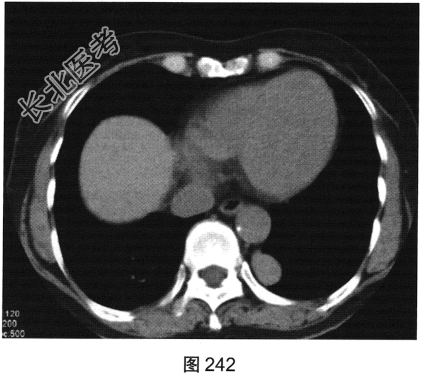

- [材料题] 患者女性,25岁。偶有胸闷,进食不畅,无咳嗽、无发热。行胸部CT检查,如图241、图242所示。

- 多项选择题1.对病灶的正确描述是( )

A、可见分叶

B、病灶位于左肺下叶内前基底段

C、病灶可能起源于左下后肋

D、胸膜凹陷征

E、宽基底于胸膜相连

F、病灶可能起源于胸膜

G、边缘光滑

H、病灶可能起源于椎管内